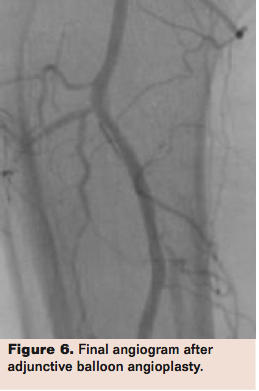

The Phoenix Atherectomy System offers an intriguing combination of features for the treatment of peripheral artery disease, particularly for vessels below the knee. With its front-cutting design; cut, capture, and clear mechanism of action; and profile down to 5 Fr, the Phoenix has the potential to treat a broad range of vessel diameters and lesion types while also reducing the chance of distal embolization. Figures 4 through 6 show a case that used the Phoenix Atherectomy System from the EASE study.

Postatherectomy angiography revealed an enlarged lumen with no evidence of dissection or lesion extension. Estimated residual stenosis was 40%. Intravascular ultrasound revealed significant lumen gain approximately 30% larger than the tip used (2.2 mm), a smooth leading intimal edge and no noted dottering effect, hematoma, or dissection. There is no further evidence of distal rouleaux formations consistent with stasis.